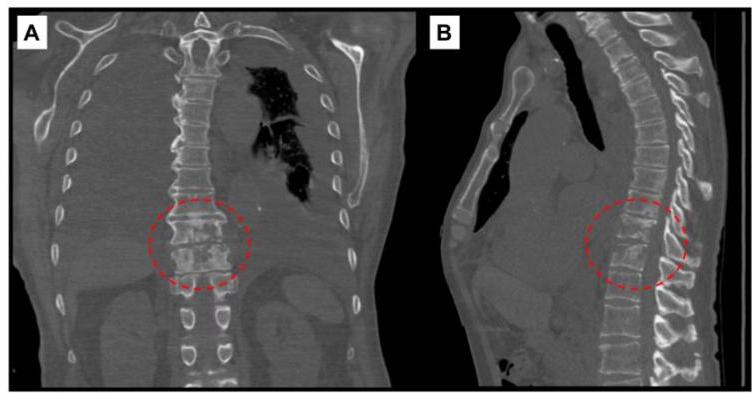

5. Skeletal Tuberculosis

- Sites: Spine (Pott disease - most common), arthritis, osteomyelitis.

- Presentation: Chronic disease with insidious onset; can develop >10 years after infection. May be mistaken for chronic osteomyelitis.

- Diagnostics: Radiographs show cortical destruction, vertebral collapse, disk space narrowing. Biopsy/culture essential.

Plain radiographs, CT, and MRI aid greatly in extrapulmonary TB diagnosis. Spinal TB shows vertebral collapse and disk space narrowing. Bone and joint TB ranges from mild effusions to massive destruction

- Spinal TB: Vertebral collapse, disk space narrowing.